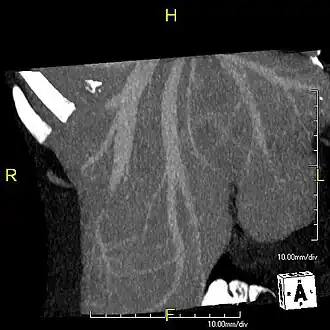

With the recent advances of noninvasive imaging, living liver donors usually have to undergo imaging examinations for liver anatomy to decide if the anatomy is feasible for donation. The evaluation is usually performed by multidetector row computed tomography (MDCT) and magnetic resonance imaging (MRI). MDCT is good in vascular anatomy and volumetry. MRI is used for biliary tree anatomy. Donors with very unusual vascular anatomy, which makes them unsuitable for donation, could be screened out to avoid unnecessary operations.

MDCT image. Portal venous anatomy contraindicated for liver donation -

MDCT image. 3D image created by MDCT can clearly visualize the liver, measure the liver volume, and plan the dissection plane to facilitate the liver transplantation procedure. -

Phase contrast CT image. Contrast is perfusing the right liver but not the left due to a left portal vein thrombus.